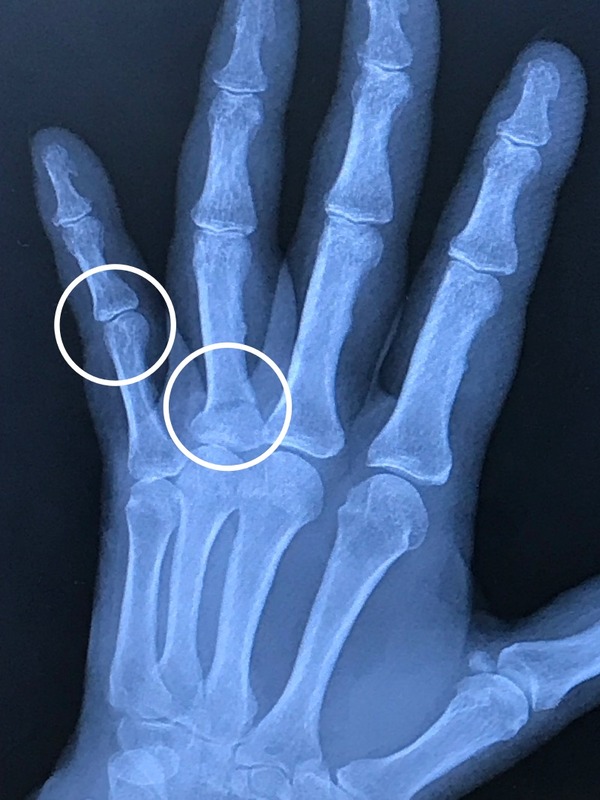

1週間ぶりに撮ったレントゲンで

新たな事実が判明。

薬指だけでなく

小指の関節の軟骨に

小さな損傷発覚。